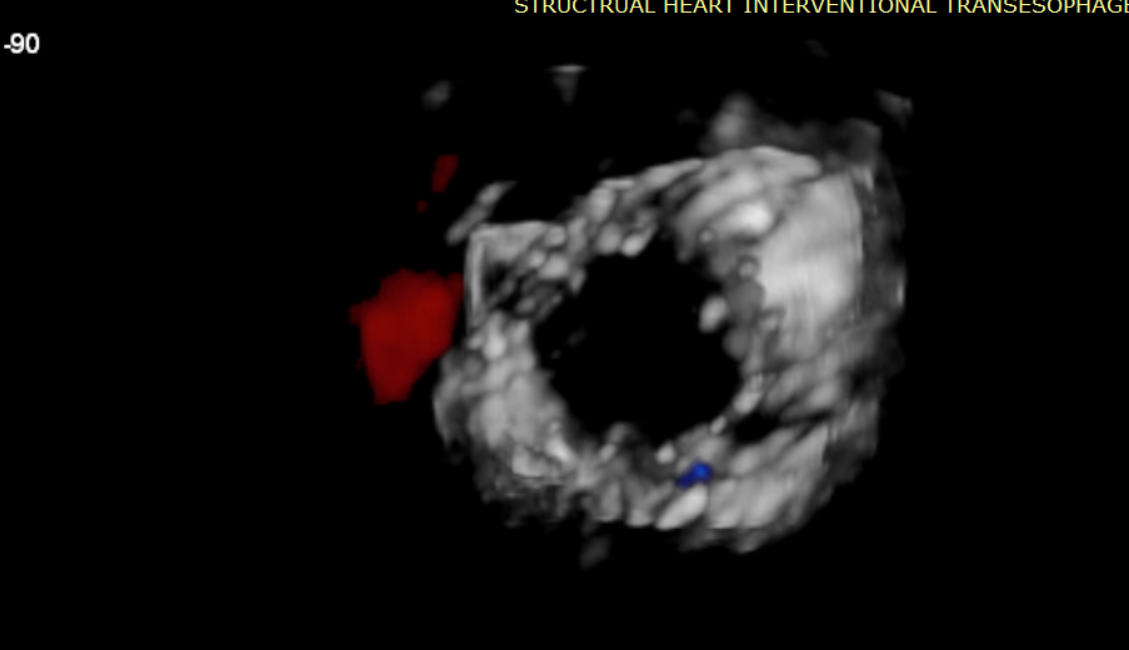

術(shù)前超聲提示大量三尖瓣反流

術(shù)中輸送器在超聲引導(dǎo)下調(diào)整位置

術(shù)后超聲提示無瓣周漏

術(shù)后超聲提示僅殘余輕微瓣周漏